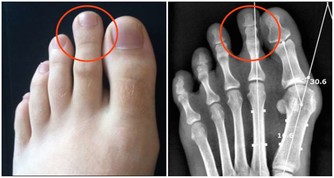

9.以及,感覺不斷腹脹;肚子腫脹;肚子或骨盆部位不舒服;吃東西時感覺飽脹或者食慾不振,這都是卵巢癌的症狀。